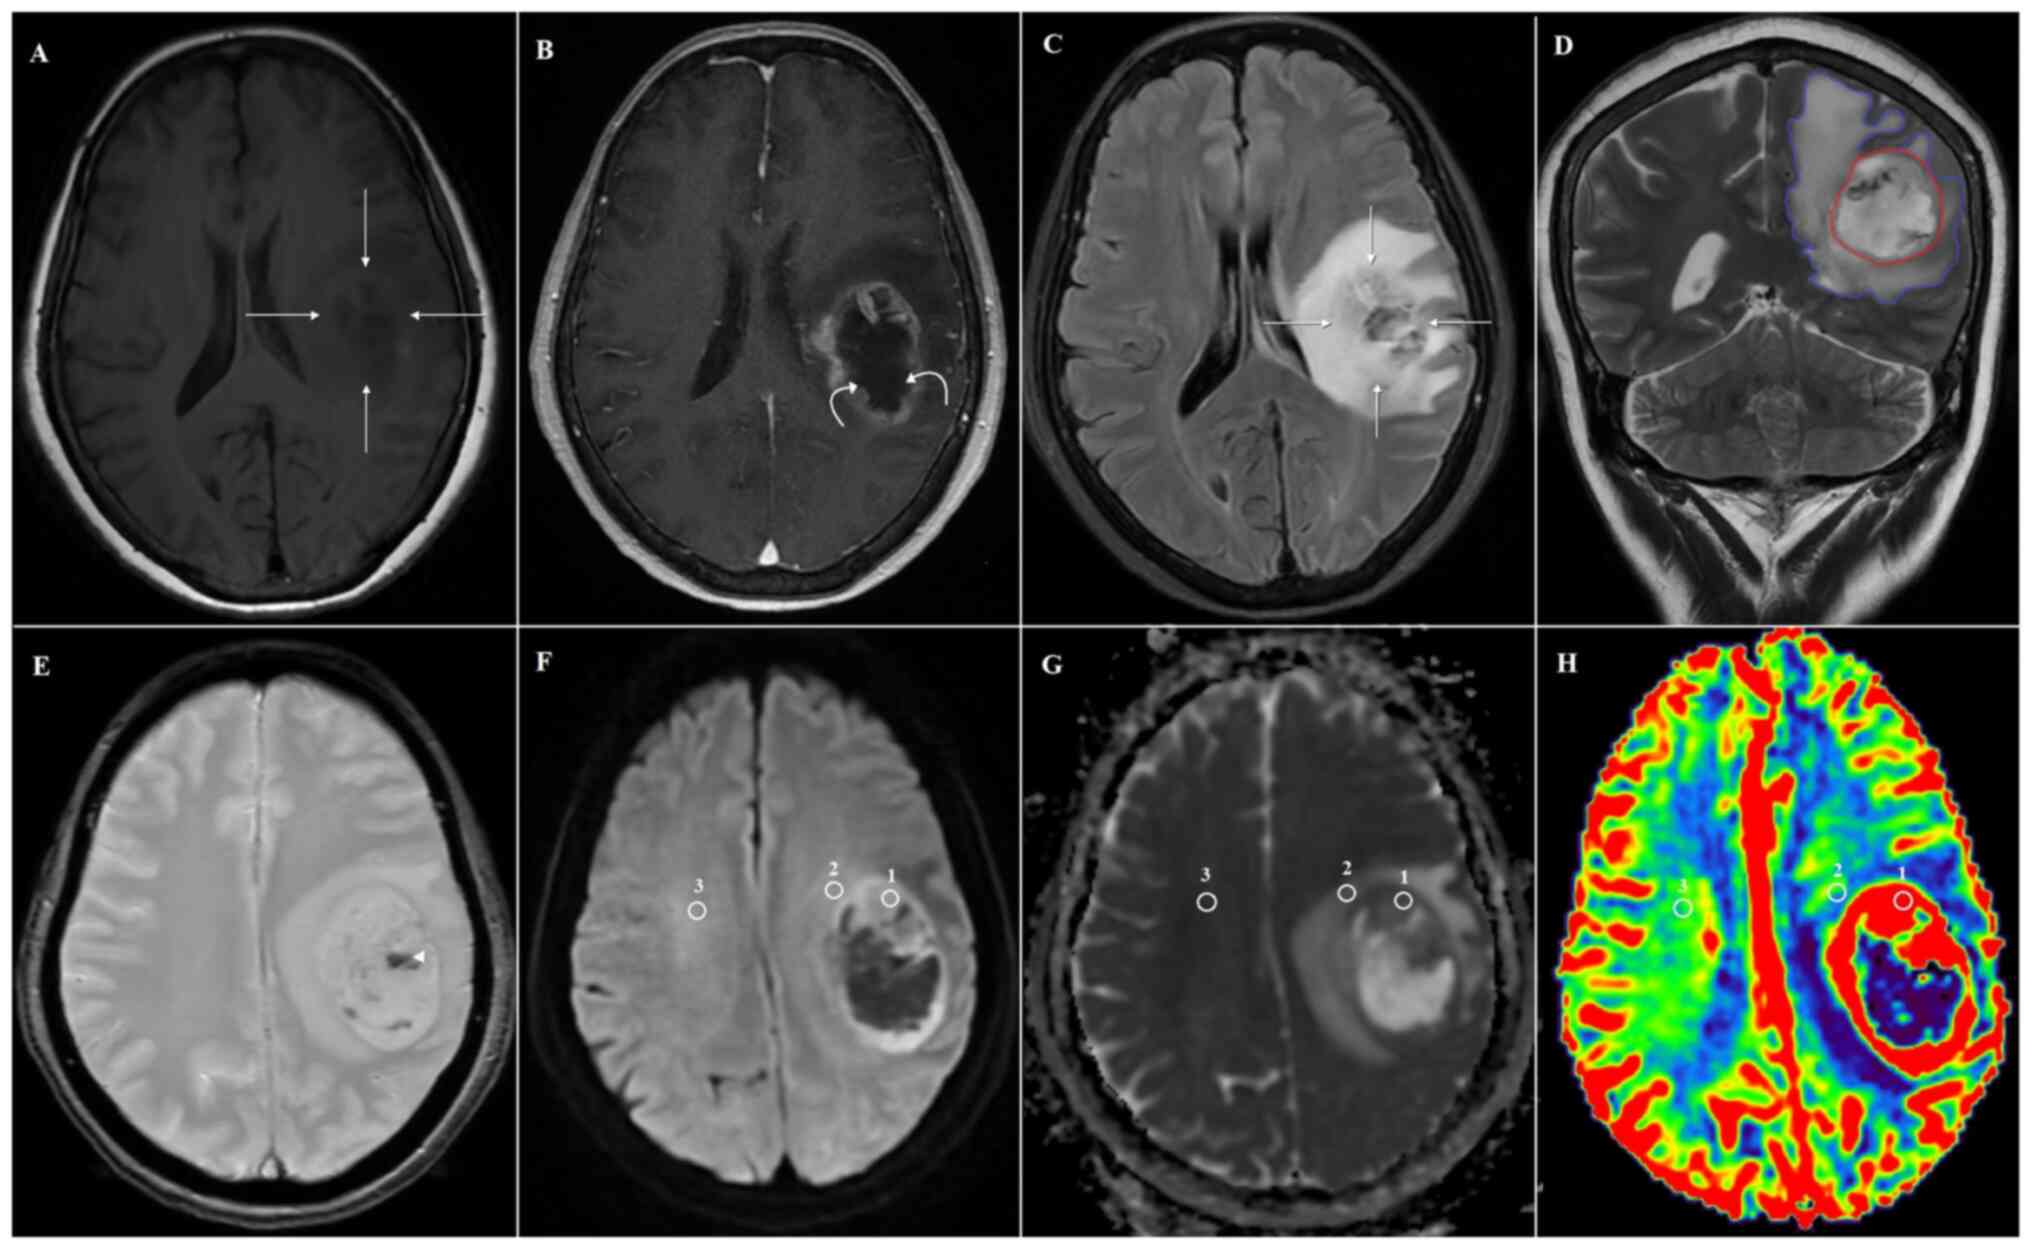

Differentiation of glioblastoma and primary central nervous system lymphomas using multiparametric diffusion and perfusion magnetic resonance imaging

The present study aimed to determine whether combining diffusion‑weighted (DWI) and dynamic susceptibility contrast‑enhanced perfusion‑weighted (DSC‑PWI) magnetic resonance imaging (MRI) could differentiate between primary central nervous system lymphoma (PCNSL) and glioblastoma (GBM). The present retrospective study evaluated 45 patients with histologically confirmed brain tumors, of which 18 had PCNSLs and 27 had GBMs. All patients underwent conventional, DWI, and DSC‑PWI MRIs before the surgical removal of the lesion or stereotactic biopsy. The solid tumor component, peritumoral edema, and abnormal white matter were measured in three regions of interest to evaluate relative cerebral blood volume (rCBV), apparent diffusion coefficient (ADC) and DWI. In conventional MRI, there were significant differences in tumor numbers, tumor enhancement type, tumor necrosis, hemorrhage and open‑ring sign between GBM and PCNSL. Solid tumor ADC and rCBV values (ADCt and rCBVt, respectively) and their ratios with abnormal white matter amounts were significantly higher in GBM cases than in PCNSL cases (P<0.05). The rCBV value for peritumoral edema (rCBVe) and its ratio with abnormal white matter amount (rCBVe/n) were significantly higher in GBM cases than in PCNSL cases (P<0.05). However, ADC values did not differ significantly for peritumoral edema. DWI values did not differ significantly. Combining rCBVt and rCBVe/n provided a perfect area under the receiver operating characteristic curve of 1.00, with 100% sensitivity and 100% specificity for distinguishing GBM from PCNSL. In the results of the present study, the major criterion in the decision‑making process distinguishing PCNSL from GBM was the combined rCBVt and rCBVe/n parameter. A minor criterion was the ADCt value of the lesion.